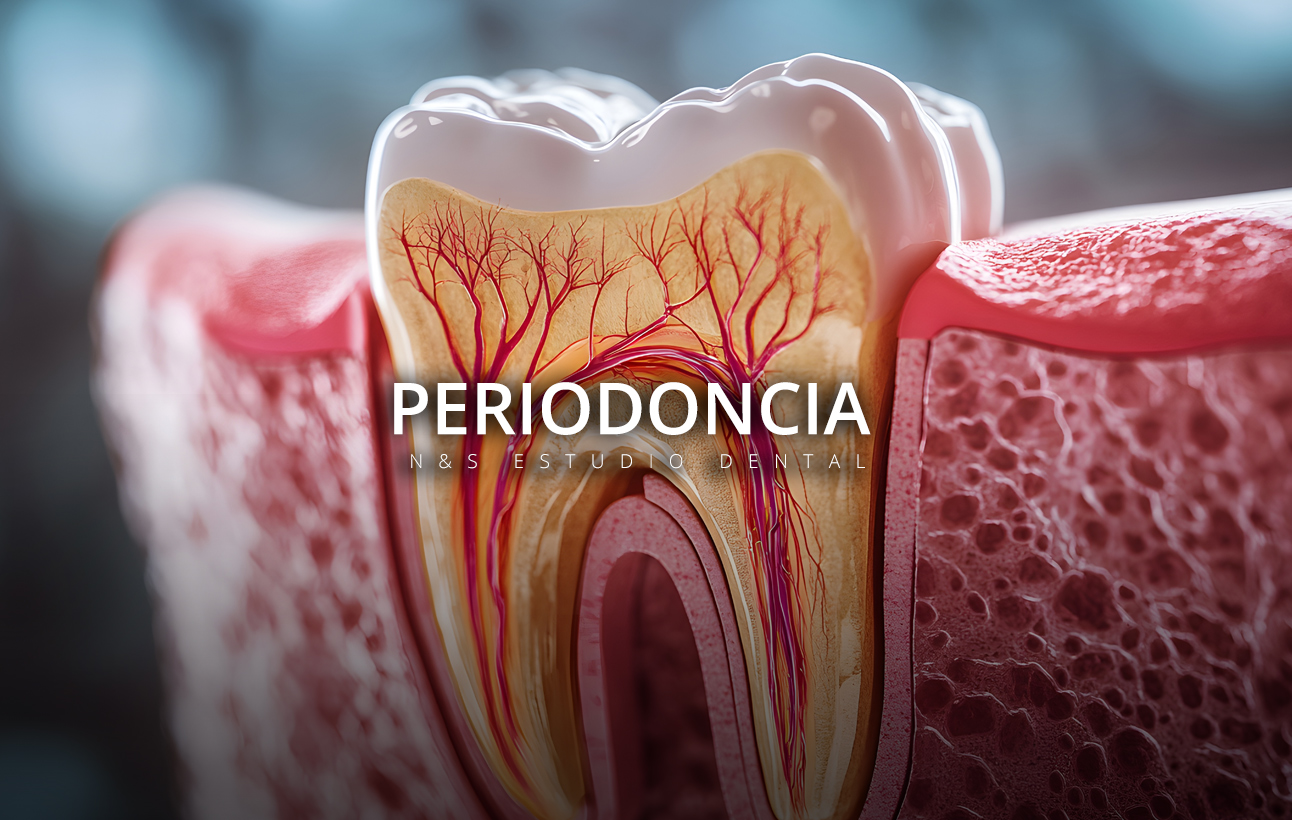

En N&S Estudio Dental entendemos que unas encías sanas son la base de una sonrisa fuerte y duradera. La periodoncia es la especialidad que se encarga de prevenir, diagnosticar y tratar las enfermedades de las encías y de los tejidos que sostienen tus dientes.

• Gingivitis: inflamación inicial de las encías, que suele presentarse con enrojecimiento, sangrado al cepillarse y, a veces, sensibilidad. Si se detecta a tiempo, es completamente reversible.

• Periodontitis: etapa más avanzada, en la que la inflamación y la infección dañan el hueso y los ligamentos que sujetan los dientes. Puede provocar movilidad dental e incluso la pérdida de piezas si no se trata.